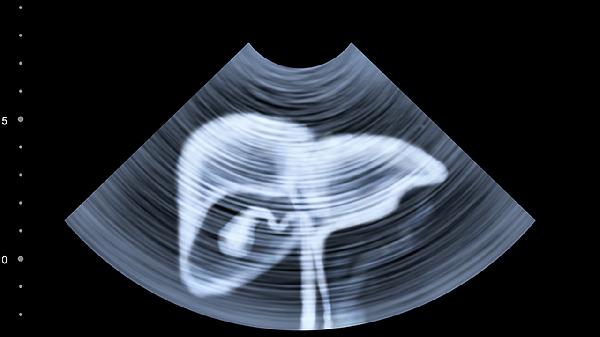

部分研究显示其成分可抑制肝脏星状细胞活化,延缓纤维化进展。适用于肝硬化前期患者,需结合影像学检查评估病情,重度肝硬化患者须联合其他治疗方案。

使用和络舒肝片期间应忌酒及辛辣食物,避免过度劳累。若出现皮肤黄染、呕血等严重症状需立即停药就医。慢性肝病患者应每3-6个月复查超声及肝功能,服药疗程需根据医生建议调整,不可自行长期服用。